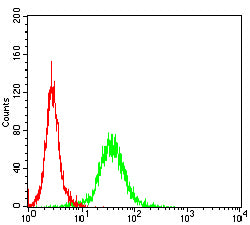

分类: 科研抗体货号: 32258别名: 2B4; NAIL; Nmrk; NKR2B4; SLAMF4应用: IF,FCM反应种属: Human

分类: 科研抗体货号: 32256别名: IMD79; OKT4D; CD4mut应用: FCM反应种属: Human